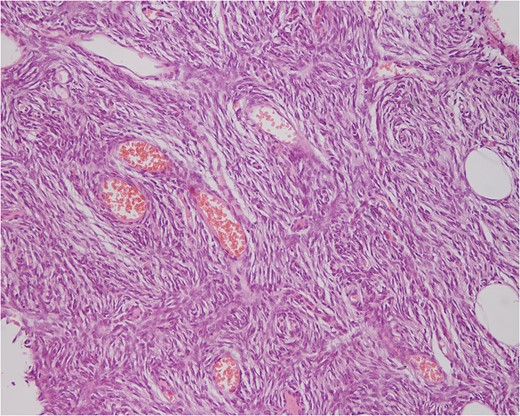

A 48-year-old woman who was born with a vascular malformation in her sternal region (Figs 1 and 2) suddenly noted a mass next to her birthmark.The patient had no significant pain or tenderness. Six months prior to presentation, in our clinic, the patient experienced embolotherapy from a vascular surgeon. As a result, the tumor grew quickly, within a period of 4 months, to a size 10–13 cm (Fig. 3). The patient was subsequently referred to the vascular Unit of Laiko University hospital in Athens. The lesion was seen projecting to the upper anterior chest wall in the sternal region. On physical examination, the mass was huge, quite firm, immobile, with no pain or tenderness in palpation. There were no palpable lymph nodes in the supraclavicular and axillary areas. Other organ examinations were normal. The laboratory studies including complete blood count test, erythrocyte sedimentation rate and C-reactive Proteins were within the normal range.MRI showed a large mass to the upper anterior chest wall most compatible with vascular malformation and there was no evidence of pectoralis major or bone involvement. The patient underwent surgical resection of the tumor (Fig. 4). Histopathology and immunochistochemical staining findings were consistent with the diagnosis of DFSP-FS with close margins and the patient reffered 2 months later to the Sarcoma Unit of Greek Anticancer Institute. We performed a wide local excision with a 3–4 cm margin (Fig. 5) all around the vertical scar in the sternal region. A part of left pectoralis major and the outer layer of the sternal body were also resected. Bilateral, pectoralis major muscle advancement flaps and a full thickness skin graft from the abdominal wall were used to cover the defect resulting from the excision (Figs 6 and 7). Biopsy revealed a residual tumor with a diagnosis of fibrosarcomatous dermatofibrosarcoma (DFSP-FS). Immunohistochemical staining was positive for CD34 (Fig. 8) with rare areas of negative expression. The dermis observed with increased vascularity,a presence of vascular congestion compatible with vascular malformation and a coexistence of scar tissue, suture granulomas and chronic inflammation. The excision margins were clear and radiation therapy was recommended because of the fibrosarcomatous type (Figs 9 and 10).

n the wide excision a coincidence of a vascular malformation/carvenous hemangioma in the upper dermal of the neoplasm (DFSP-FS).